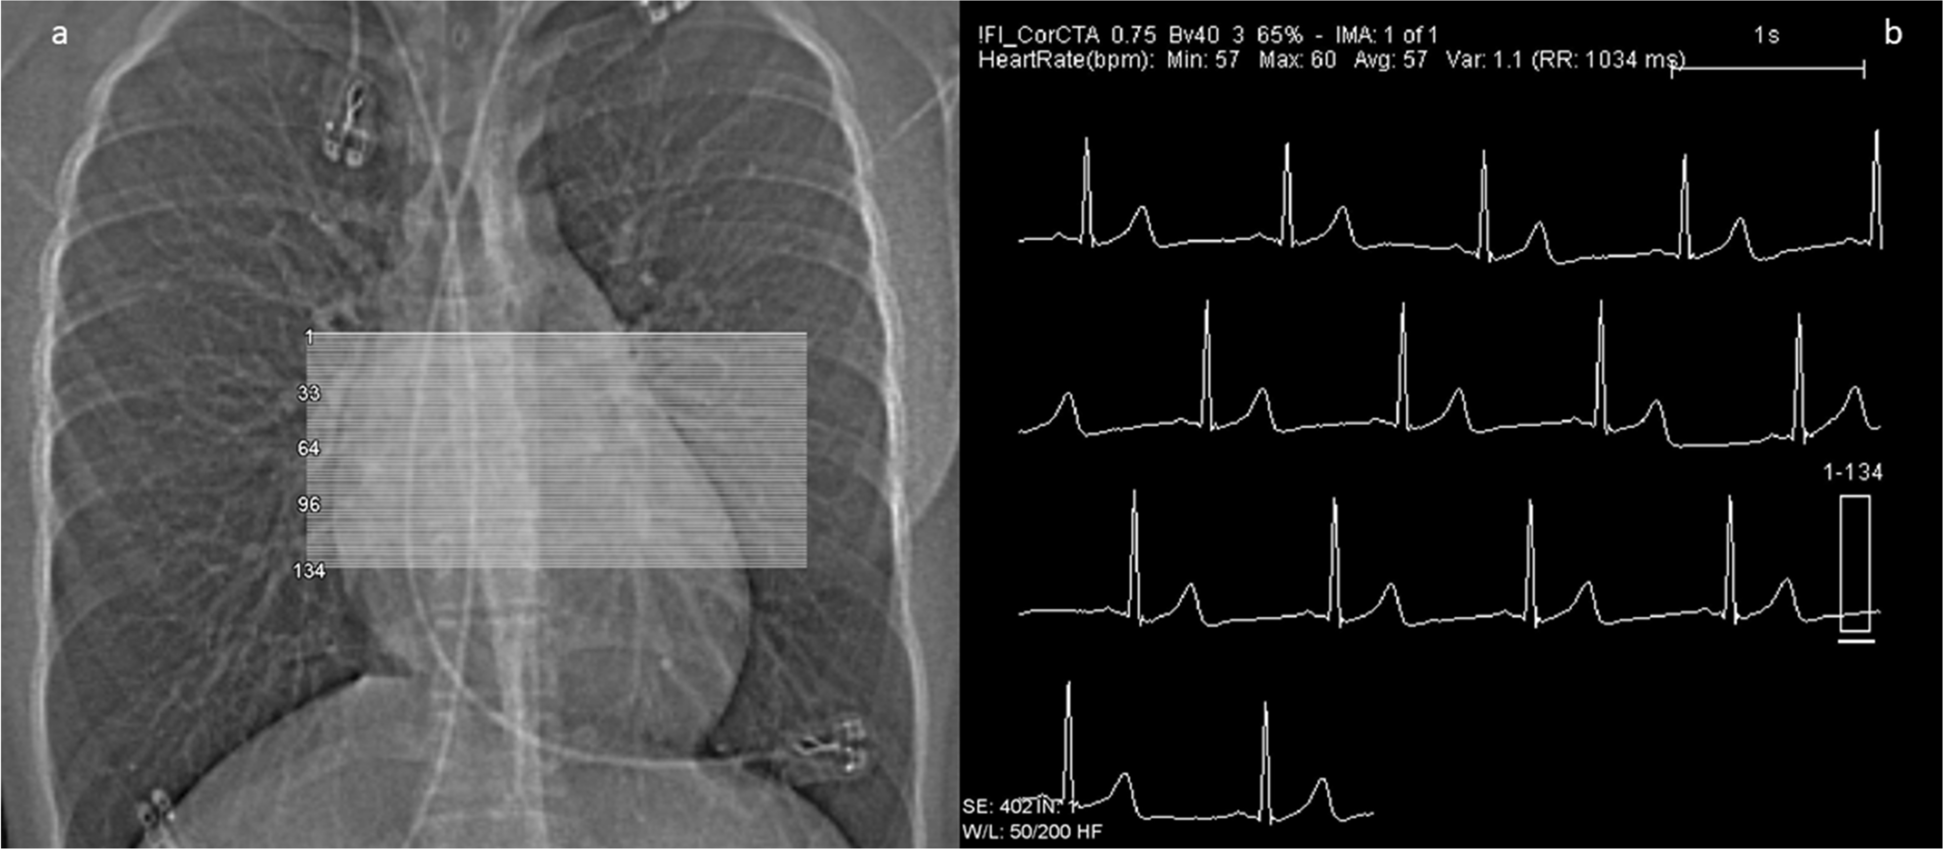

The CT examination encompasses distinct steps, which are summarized in Figs. 2 and 3.

Fig. 2

(Planning and dose monitoring): first steps are a fast low-dose overview (“topogram/sinogram”; left) and a stable ECG monitoring (right) for triggering (prospective mode) or gating (retrospective mode). Figures 2 and 3 derive from the CT of a 15-year-old girl after surgical repair of a malignant coronary anomaly (origin of the left main from the right coronary sinus) with reinsertion of the left main coronary artery with an ultra-low radiation dose (total DLP 9 mGycm ~ 0.2 mSv)